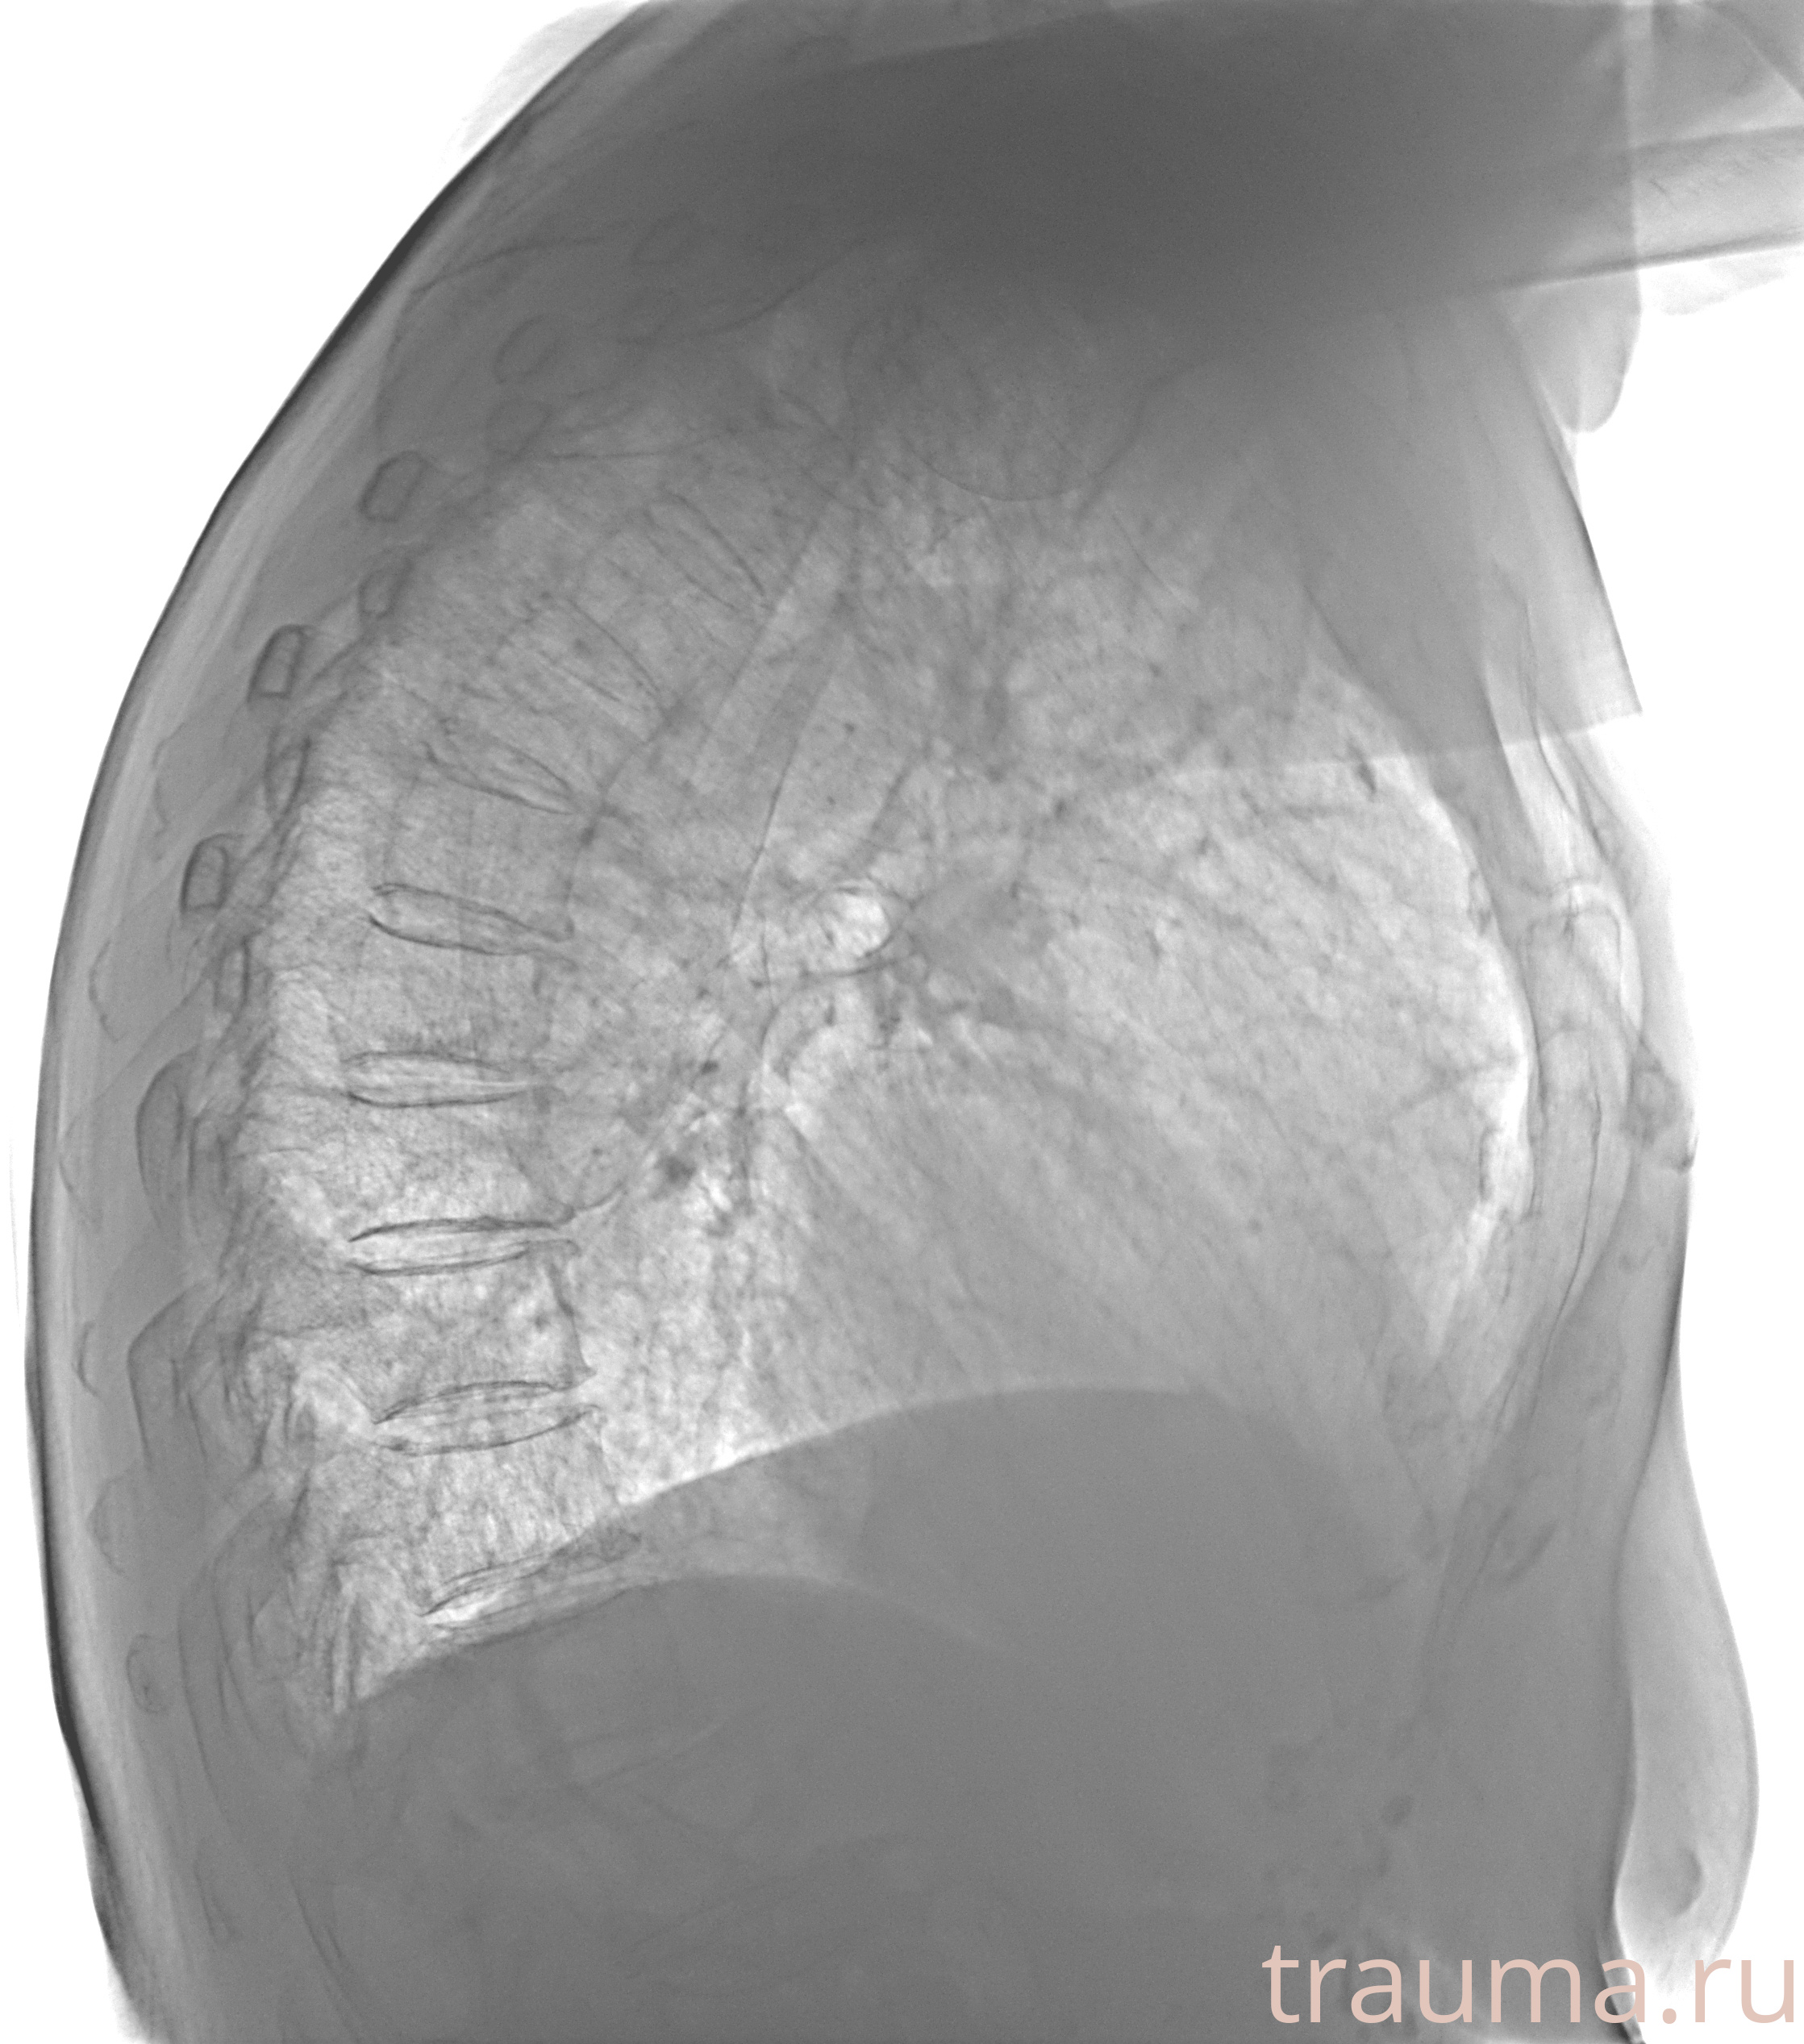

Рентген на дому: по вашему адресу приезжает врач-рентгенолог, травматолог-ортопед с мобильным рентгеновским аппаратом, проводит диагностику травмы или заболевания, делает необходимые рентгенограммы, дает рекомендации по дальнейшему лечению. Получить качественные снимки в домашних условиях возможно благодаря уникальной методике, разработанной МосРентген Центром для института  Склифосовского